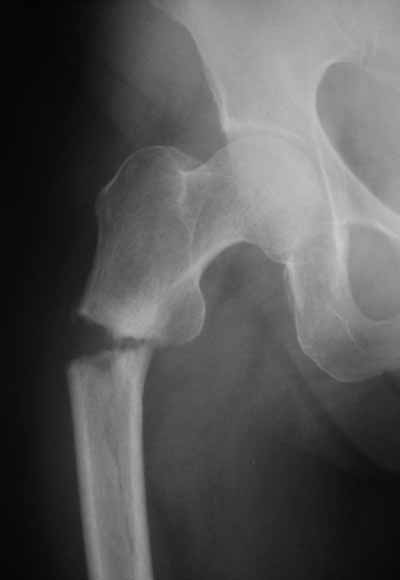

> Я имею ввиду довольно редкий простой поперечный перелом на 1-2 см

> ниже малого вертела.

Тут шеечный винт не фиксировал бы периферический отломок, так что конечно, дистальный винт был бы нужен. Хотя для такого перелома вообще короткий штифт какой-то неуютный выбор.

Не думаю так. см вложение.

> Не думаю так. см вложение.